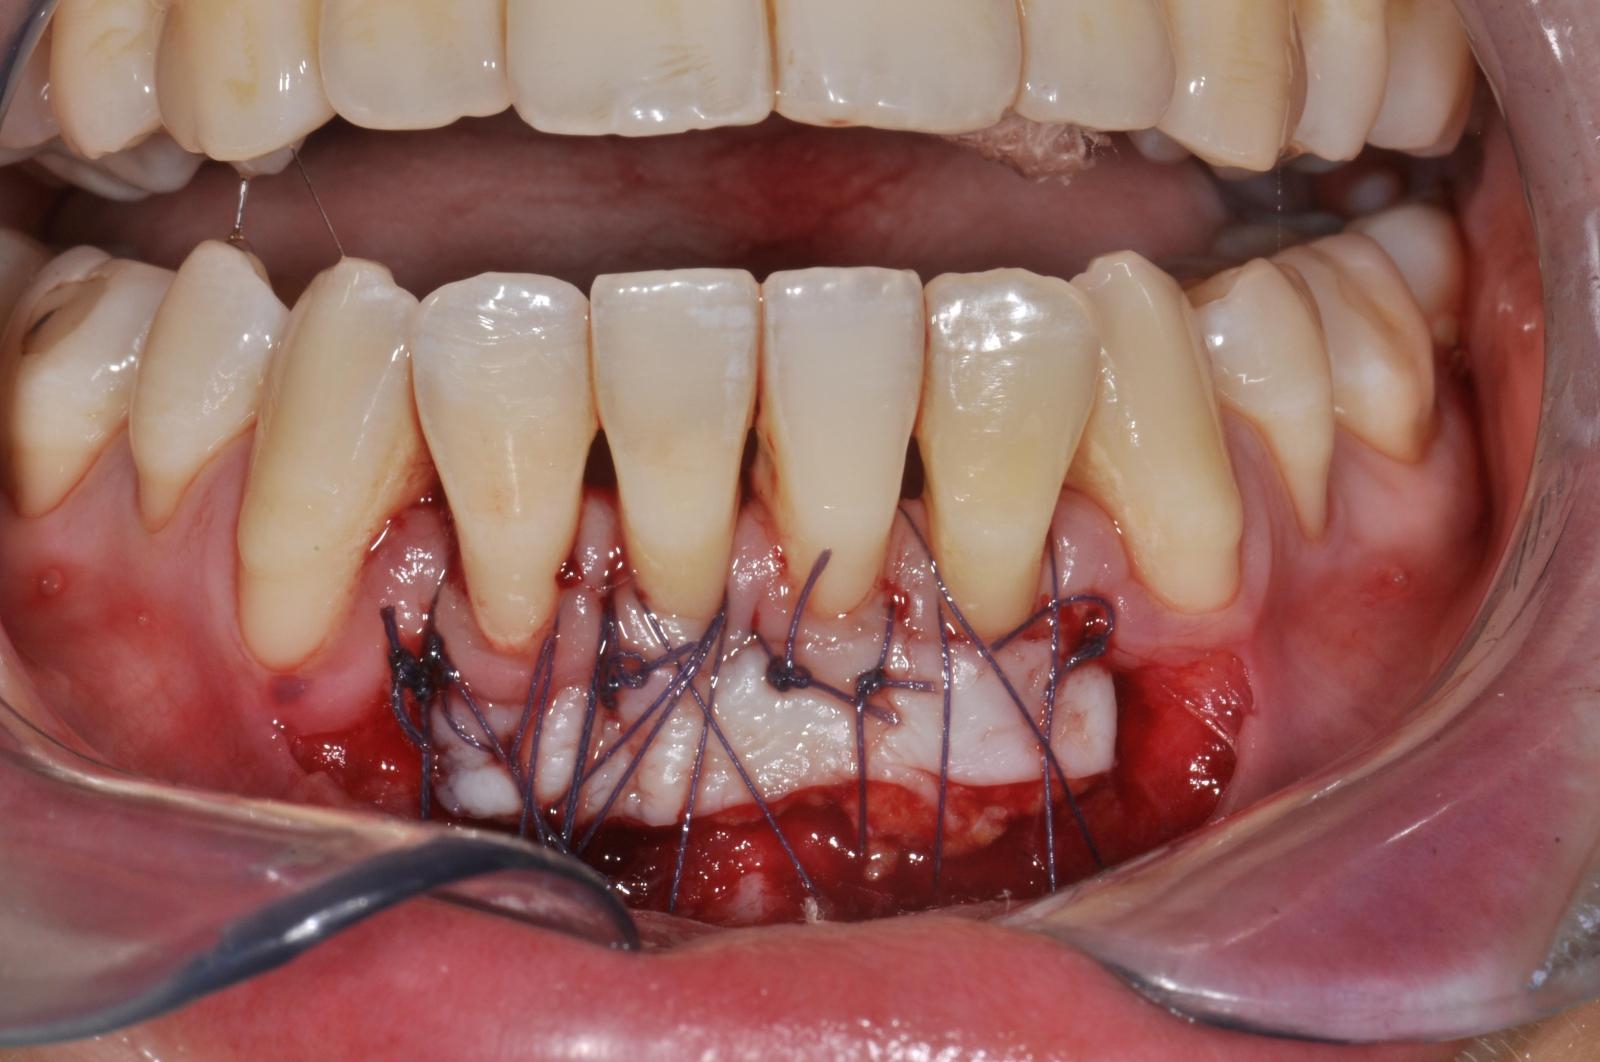

Celles-ci incluent la chirurgie à lambeaux pour un nettoyage en profondeur, la greffe gingivale ou conjonctive afin de renforcer les tissus, et la chirurgie du sourire gingival (ou "Gummy Smile") pour réharmoniser l’esthétique du sourire.

- Greffe Gingivales et conjonctives